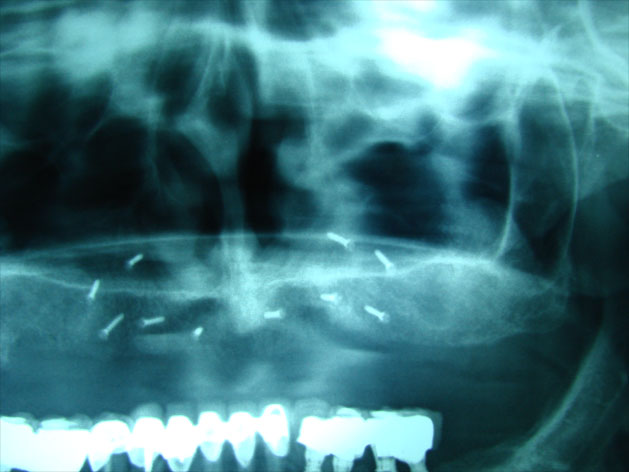

Existen muchas situaciones donde la pérdida y la atrofia ósea son tan graves que nos obligan a recurrir a la cresta iliaca del paciente, para conseguir el volumen óseo necesario para la correcta reconstrucción del maxilar. Así, la colocación de implantes será posible a los 3 meses.